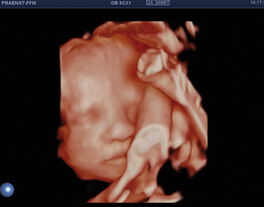

Organscreening (Fehlbildungsausschluss)

Diese „zweite“ große Ultraschalluntersuchung wird am besten in der 20+0 SSW bis 23+0 SSW durchgeführt.

Beim Organscreening oder Fehlbildungsausschluss wird die Entwicklung Ihres Kindes genau beurteilt. Nach den Richtlinien der DEGUM zeigen und erklären wir Ihnen umfassend alle bedeuteten sonografischen Merkmale Ihres Kindes. So können wir Ihn in der Regel zeigen, dass sich Ihr Kind ganz normal entwickelt.